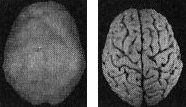

Наконец, рис. Г показывает трехмерную картину активности здорового мозга, вид снизу, а под ней находится иконка с моделью мозга в той же проекции. ![]() Помните, что трехмерные поверхностные сканы помогают увидеть малоактивные области, а трехмерные функциональные сканы помогают обнаружить гиперактивные области. Как не бывает двух одинаковых лиц, так нельзя встретить и два одинаково выглядящих мозга. С эстетической точки зрения бывают красивые и уродливые, банальные и причудливые мозги. Но всегда справедливо — и это доказали 30 000 проведенных мною сканирований, — что активность здорового мозга должна быть достаточной, полной, равномерной и симметричной. В здоровом мозге целы все важные участки, и все они работают гармонично. Возрастные вариации нормальны. Сканы мозга детей и подростков показывают большую активность, чем у взрослых. Но даже у пожилых людей мозг будет здоровым, если о нем заботились в течение жизни. Давайте взглянем на несколько примеров здорового и не очень здорового мозга. Однажды я предложил студентам стать добровольцами в исследовании функционирования мозга. Кристи, одна из вызвавшихся, воскликнула: «Вам обязательно нужно проверить мою бабушку Анну. Ей 82 года, но среди всех, кого я знаю, она одна из самых нормальных. Она вам понравится!» Бабушка согласилась, и мы провели томографию. Действительно, обнаружилось, что мозг этой пожилой женщины здоров, а ее жизнь соответствует всем критериям профилактики здоровья мозга (она не употребляла наркотики, не получала травм головы, не имела родственников первой степени с психиатрическими заболеваниями и т. д.). В течение 58 лет Анна была замужем, всегда оставаясь любящей женой, матерью и бабушкой, ее ум был острым и деятельным. Кроме того, она активно участвовала в делах местной церкви и муниципалитета. Она создала прочные и длительные отношения с родными и друзьями. Скан мозга Анны — один из самых здоровых в моей базе данных (рис. 2.5 и 2.6). Скан здорового мозга Анны, 82 года Рис. 2.5 Вид сверху Полная симметричная активность ![]() Рис. 2.6 Вид снизу Полная симметричная активность ![]() Двадцатилетний Брюс, несмотря на молодость, годами злоупотреблял наркотиками: героином, марихуаной, амфетаминами, галлюциногенами, экстази и обезболивающими. Я познакомился с ним, когда снимал образовательный фильм о вреде наркотиков. Брюс не был способен завязать со своим пристрастием. Отношения с родными разладились. Он стыдился себя и своего поведения. Как вы сами можете увидеть, мозг 82-летней Анны на томограмме выглядит значительно здоровее поврежденного наркотиками мозга молодого Брюса (рис. 2.7). Поврежденный наркотиками мозг Брюса Рис. 2.7 Вид сверху Значительные повреждения ![]() В норме с возрастом мозг становится все менее активным, поэтому если очень пожилая женщина обладает значительно более здоровым мозгом, чем 20-летний парень, значит, у этого парня серьезные неприятности. Я убедился, что люди со здоровым мозгом ведут себя эффективно и всегда движутся к поставленным целям. Они прекрасные сотрудники, супруги, родители, друзья и граждане. Люди же с поврежденным мозгом с трудом бредут по жизни. Вспомните про болезнь Альцгеймера (БА): можно ли сказать, что заболевшие ею способны полноценно проявлять свою волю и личность? Вероятно, нет. У людей с БА функционал мозга значительно поврежден. От этой болезни страдала мать моей подруги Айзы Гиббонс, основавшей ряд центров поддержки для людей с БА и членов их семей. Мать Лизы из доброй, мягкой женщины превратилась в озлобленного, иррационального и агрессивного человека (рис. 2.8). Мозг пациента с болезнью Альцгеймера Рис. 2.8 Вид сверху Значительно снижена активность в задних частях мозга ![]() Гиперактивность мозга часто связана с обсессивно-компульсивным [2] и биполярным расстройствами и другими заболеваниями. 17-летняя Хитер очень много пила и не ладила с семьей. Я сделал томографию мозга ей и ее брату для телепередачи «Правда о выпивке», которая позже получила премию «Эмми». На сканах вы видите области очень высокой активности (рис. 2.9). Неудивительно, что девушка начала пить — она пыталась успокоить свой мозг. Гиперактивный мозг Хитер Рис. 2.9 Вид функциональной активности снизу Значительно снижена общая активность ![]() 45-летний Джимми обратился ко мне с посттравматическим стрессовым расстройством, вызванным пожаром. Томограмма показала множественные области повышенной активности, о которых можно было догадаться, судя по его тревожности, депрессии и страхам. Эмоциональные центры его мозга работали чересчур напряженно, и моей задачей было их успокоить (рис. 2.10). Гиперактивный мозг Джимми Рис. 2.10 Вид функциональной активности снизу Повышенная активность в глубоких областях мозга ![]() А теперь вернемся к разнице между «волевым» и «мозговым поведением». Плохо работающий мозг лишает людей силы воли и провоцирует деструктивные поступки. Люди с обсессивно-компульсивным расстройством (ОКР), синдромом Туретта (СТ) или зависимостью от наркотиков, скорее всего, стали жертвами своего мозга. Для ОКР характерны вызывающие огорчение навязчивые мысли или компульсивное поведение (непрерывная проверка дверных замков, постоянное мытье рук, следование ритуалам). Даже если человек понимает, что его мысли и поступки иррациональны, он все равно не может от них отказаться. В тяжелых случаях такие мысли и действия занимают большую часть дня. Сканы показывают, что при ОКР гиперактивна передняя часть мозга, провоцирующая навязчивые мысли (обсессия) или действия (компульсия). |